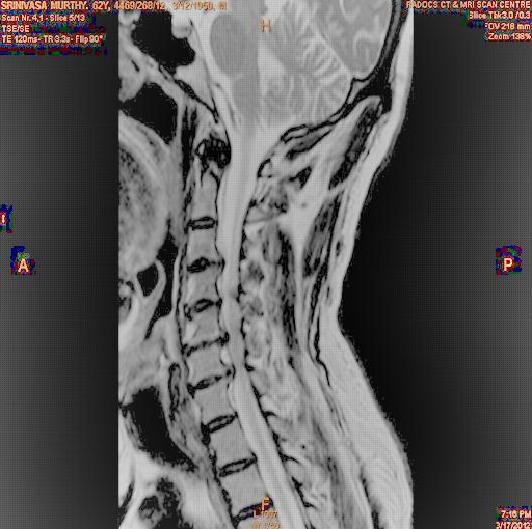

The proposed algorithm uses HSV color space to enhance spinal cord images since this color space offers many advantages such as color separation from intensity, reduced color distortion and efficient enhancement. The algorithm proposed takes advantage of this color space by performing enhancment operation on the intensity or value component and preserving the color information. The first column of Fig. 3 shows the original spinal cord test images followed by the extraction of value component presented in second column. Next, the third column of Fig. 3 shows the value component enhanced using the proposed multirate multiscale retinex algorithm. The modified version of the retinex algorithm presented here is capable of producing high quality reconstructed pictures, far better than the other researchers method.

The developed algorithm presented in the previous section was coded using Matlab Version 8.0. The experiment was conducted by considering poor quality spinal cord images of having various lesions. The first column of Fig. 4 shows the axial view of neck spinal cord images of size pixels, respectively. The second column of Fig. 4 presents the same images enhanced using histogram equalization. As is evident from the results presented, the histogram equalization method performs global image enhancement operation which improves the contrast of an image but at the cost loss in image details. The third column of Fig. 4 shows the MSR based spinal cord image enhancement. It can be seen that from the result presented, MSR scheme improves the details that are not clearly visible in histogram equalization technique. In general, image enhancement achieved by MSR method is better compared to histogram equalization. However, the MSR method voilates gray world assumption. Therefore, the image enhanced by this scheme appears to be grayish. Although, numerous work have been reported for solving the problem due to gray world voilation, no work seems to developed for complete elimination.

The fourth column of Fig. 4 shows the image enhanced using Chao et al. []. It can be seen from the results presented that the reconstructed images of Chao’s method have black spots. The appearance of these dark patches degrades the visual quality of the enhanced image. The image enhanced using proposed multirate multiscale retinex image enhancement method presented in the fifth column of Fig. 4, overcomes the drawback of the Chao’s method. As we can see from the simulation results, image enhancement achieved by the proposed method has improved details with significant contrast enhancement. The enhanced images from the proposed method provides information to physicians, radiologists and researchers for various types of pathology detection.